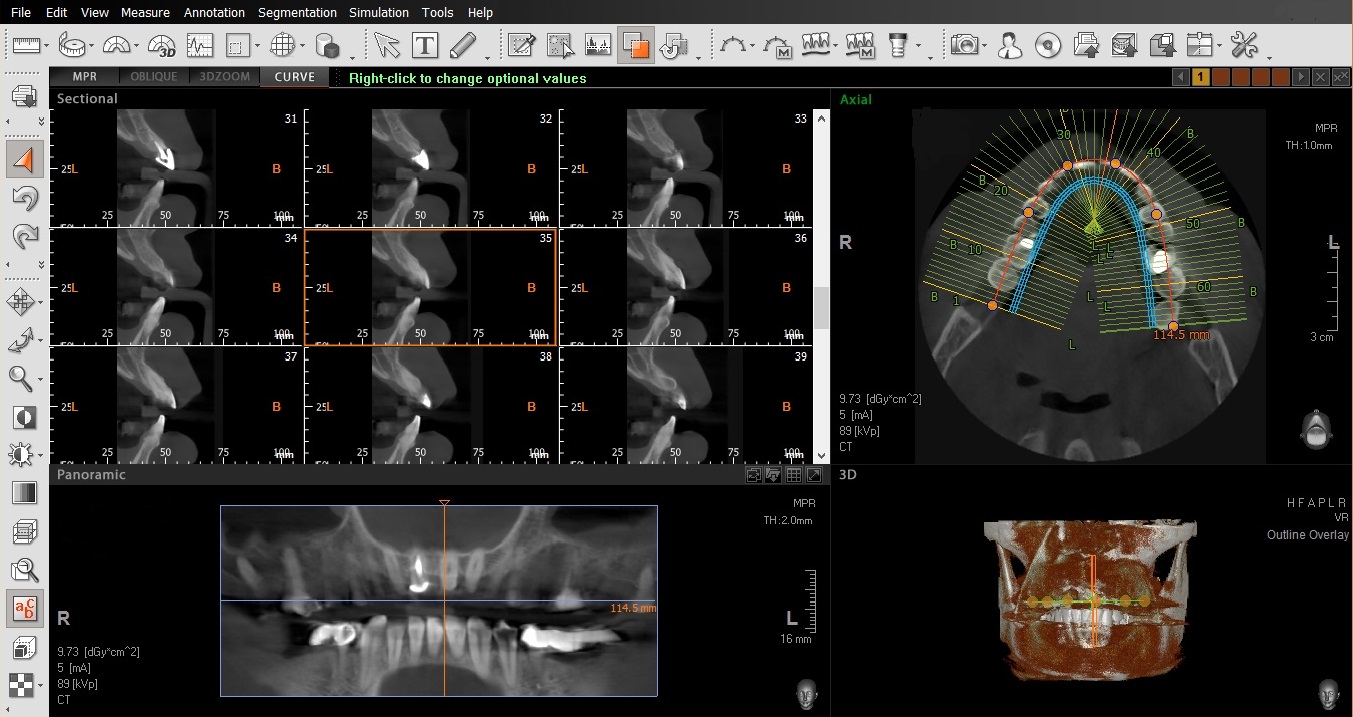

+ Phim X-quang CT: cung cấp hình ảnh 3 chiều chi tiết toàn

bộ cấu trúc vùng hàm; giúp đánh giá đúng chất lượng xương

(độ đặc loãng) và số lượng xương, xác định dây thần kinh

hàm dưới,.. và đặc biệt trong phẫu thuật cấy ghép Implant,

phim X-quang – CT giúp chọn đúng vị trí và hướng cắm Implant.